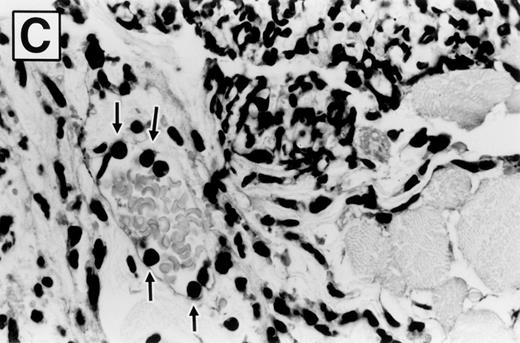

Photomicrographs of hematoxylin and eosin-stained sections of ears 8 hours after zymosan injection, in wild-type and E-/P-selectin double-deficient mice, are shown in Fig 5. The ear is composed of a strip of cartilage covered on each side with loose connective tissue and skin. Bundles of skeletal muscle are present within the connective tissue on the dorsal aspect of the ear. PBS-injected ears were characterized by disruption of the loose subcutaneous connective tissue. However, no significant inflammatory infiltrate or edema fluid was observed. Zymosan-injected ears from both wild-type (Fig 5A) and selectin-deficient mice (Fig 5B) are characterized by deposits of zymosan particles within edematous tissue. The deposits were rimmed and effectively walled off by a layer of phagocytic cells, which are predominately PMNs. These cells had phagocytized zymosan particles that pushed their nucleus to the outer region of cytoplasm, distorting their morphology. The tissue peripheral to these micro-abscesses contained an inflammatory infiltrate of varying intensity composed primarily of PMNs, with occasional mononuclear cells, mast cells, and eosinophils in similar proportions among genotypes. Blood vessels were readily identified that contained marginated PMNs (Fig 5C). Qualitatively, the inflammatory response was similar between wild-type and selectin-deficient mice. Figure 5B shows that the PMNs that were able to complete vascular transmigration into the interstitial tissue in the selectin-deficient mice were fully capable of migrating through the tissue to the inflammatory focus, phagocytizing the zymosan particles, and participating in walling off of the inflammatory material. The inflammatory infiltrate was less intense overall in the E-/P-selectin double-deficient mice, but there was spatial variability in the intensity of the infiltrate within tissue sections, and morphologic assessment of differences between genotypes was more accurately determined by measuring whole tissue MPO content.

Photomicrographs of zymosan-injected tissue in wild-type and E- and P-selectin–deficient mice. Ear tissue was removed 8 hours after zymosan injection and sections were stained with hematoxylin and eosin. (A) Wild-type mouse (original magnification × 400). Micro-abscess consisting of aggregates of zymosan (Z) surrounded and walled off by a rim of leukocytes (between arrowheads). The leukocytes are predominantly neutrophils, many of which have distorted morphology due to having phagocytized zymosan particles. Adjacent connective tissue also contains a neutrophilic infiltrate. (B) E- and P-selectin–deficient mouse (original magnification × 400). General features are similar to those described in (A). However, the overall intensity of the leukocyte infiltrate is markedly reduced in comparison with the wild-type mouse tissue. (C) Higher magnification of inset from (A) (original magnification × 1,000). Neutrophils (arrows) adherent to endothelial cells lining a venule in the vicinity of a micro-abscess.